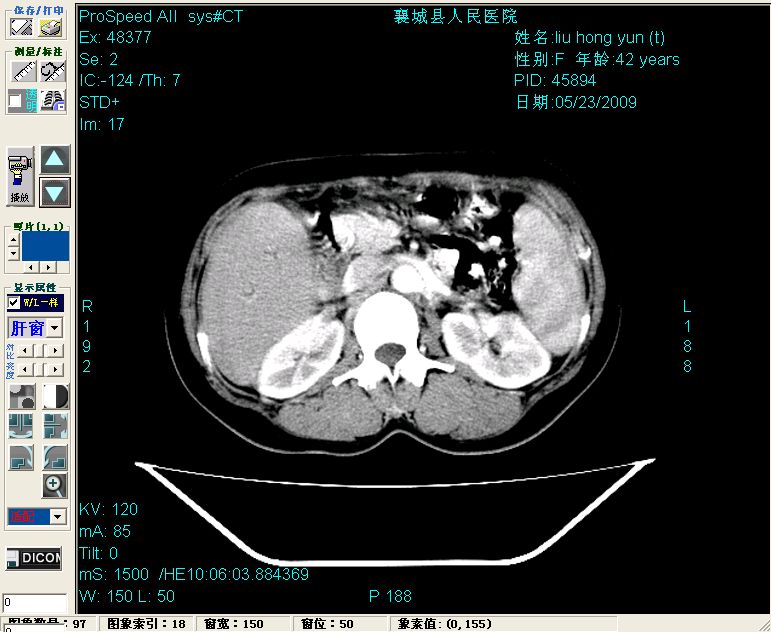

平扫:

平扫左肝外叶体积显著减小,左肝外叶见多房囊性低密度区,左肝实质及右肝前叶浅表实质呈低密度改变,左肝及右肝前叶胆管扩张,脾大

增强动脉期前述低密度区轻度早其强化,门脉期强化程度显著增高,延期扫描强化程度下降,但仍为相对高密度影

胰头部见结节状高密度影,其前方略可分辨扩强胆部管,平扫到增强始终有,但现在尚难与胃肠造影剂鉴别.

结合病史考虑,1现在引起黄疸体征的原因应该是胆总管胰段结石阻塞,建议局部胃肠造影剂排空后复查.

2左肝及右肝前叶表现考虑胆囊摘除术后所致的肝动门脉瘘形成,慢性纤维组织炎性增生.不完全除外左肝胆管细胞癌

3脾大,可能与动门脉瘘所致门脉高压有关